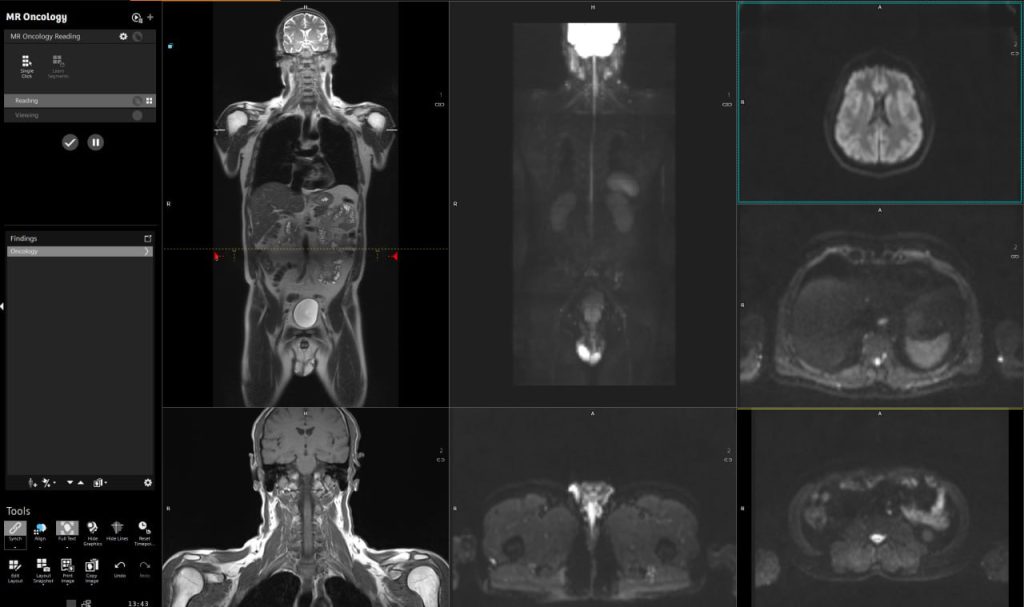

Як виглядає МРТ всього тіла?

На знімках нижче, ви можете побачити приклад МРТ всього тіла: